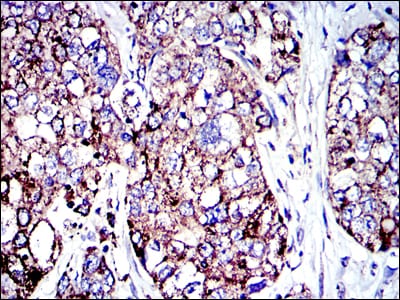

- Immunohistochemical analysis of paraffin-embedded human lung cancer tissues using AIF mouse mAb with DAB staining.